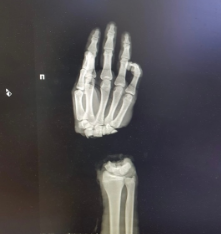

Нижегородские медики пришили кисть подростку из Коврова. Юноша поступил в ПИМУ со страшной травмой: он отрубил себе руку, когда колол дрова.

Врачи Университетской клиники ПИМУ провели операцию по реимплантации конечности.

«Сейчас состояние пациента стабильное, кровоснабжение кисти восстановлено. Понадобится еще несколько операций, чтобы восстановить функциональность кисти насколько это возможно» - рассказал ректор ПИМУ Николай Карякин.